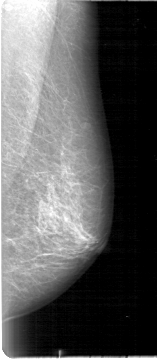

D_4012_1.LEFT_CC

LEFT_CC LINES 4621 PIXELS_PER_LINE 2101 BITS_PER_PIXEL 12 RESOLUTION 43.5 NON_OVERLAY